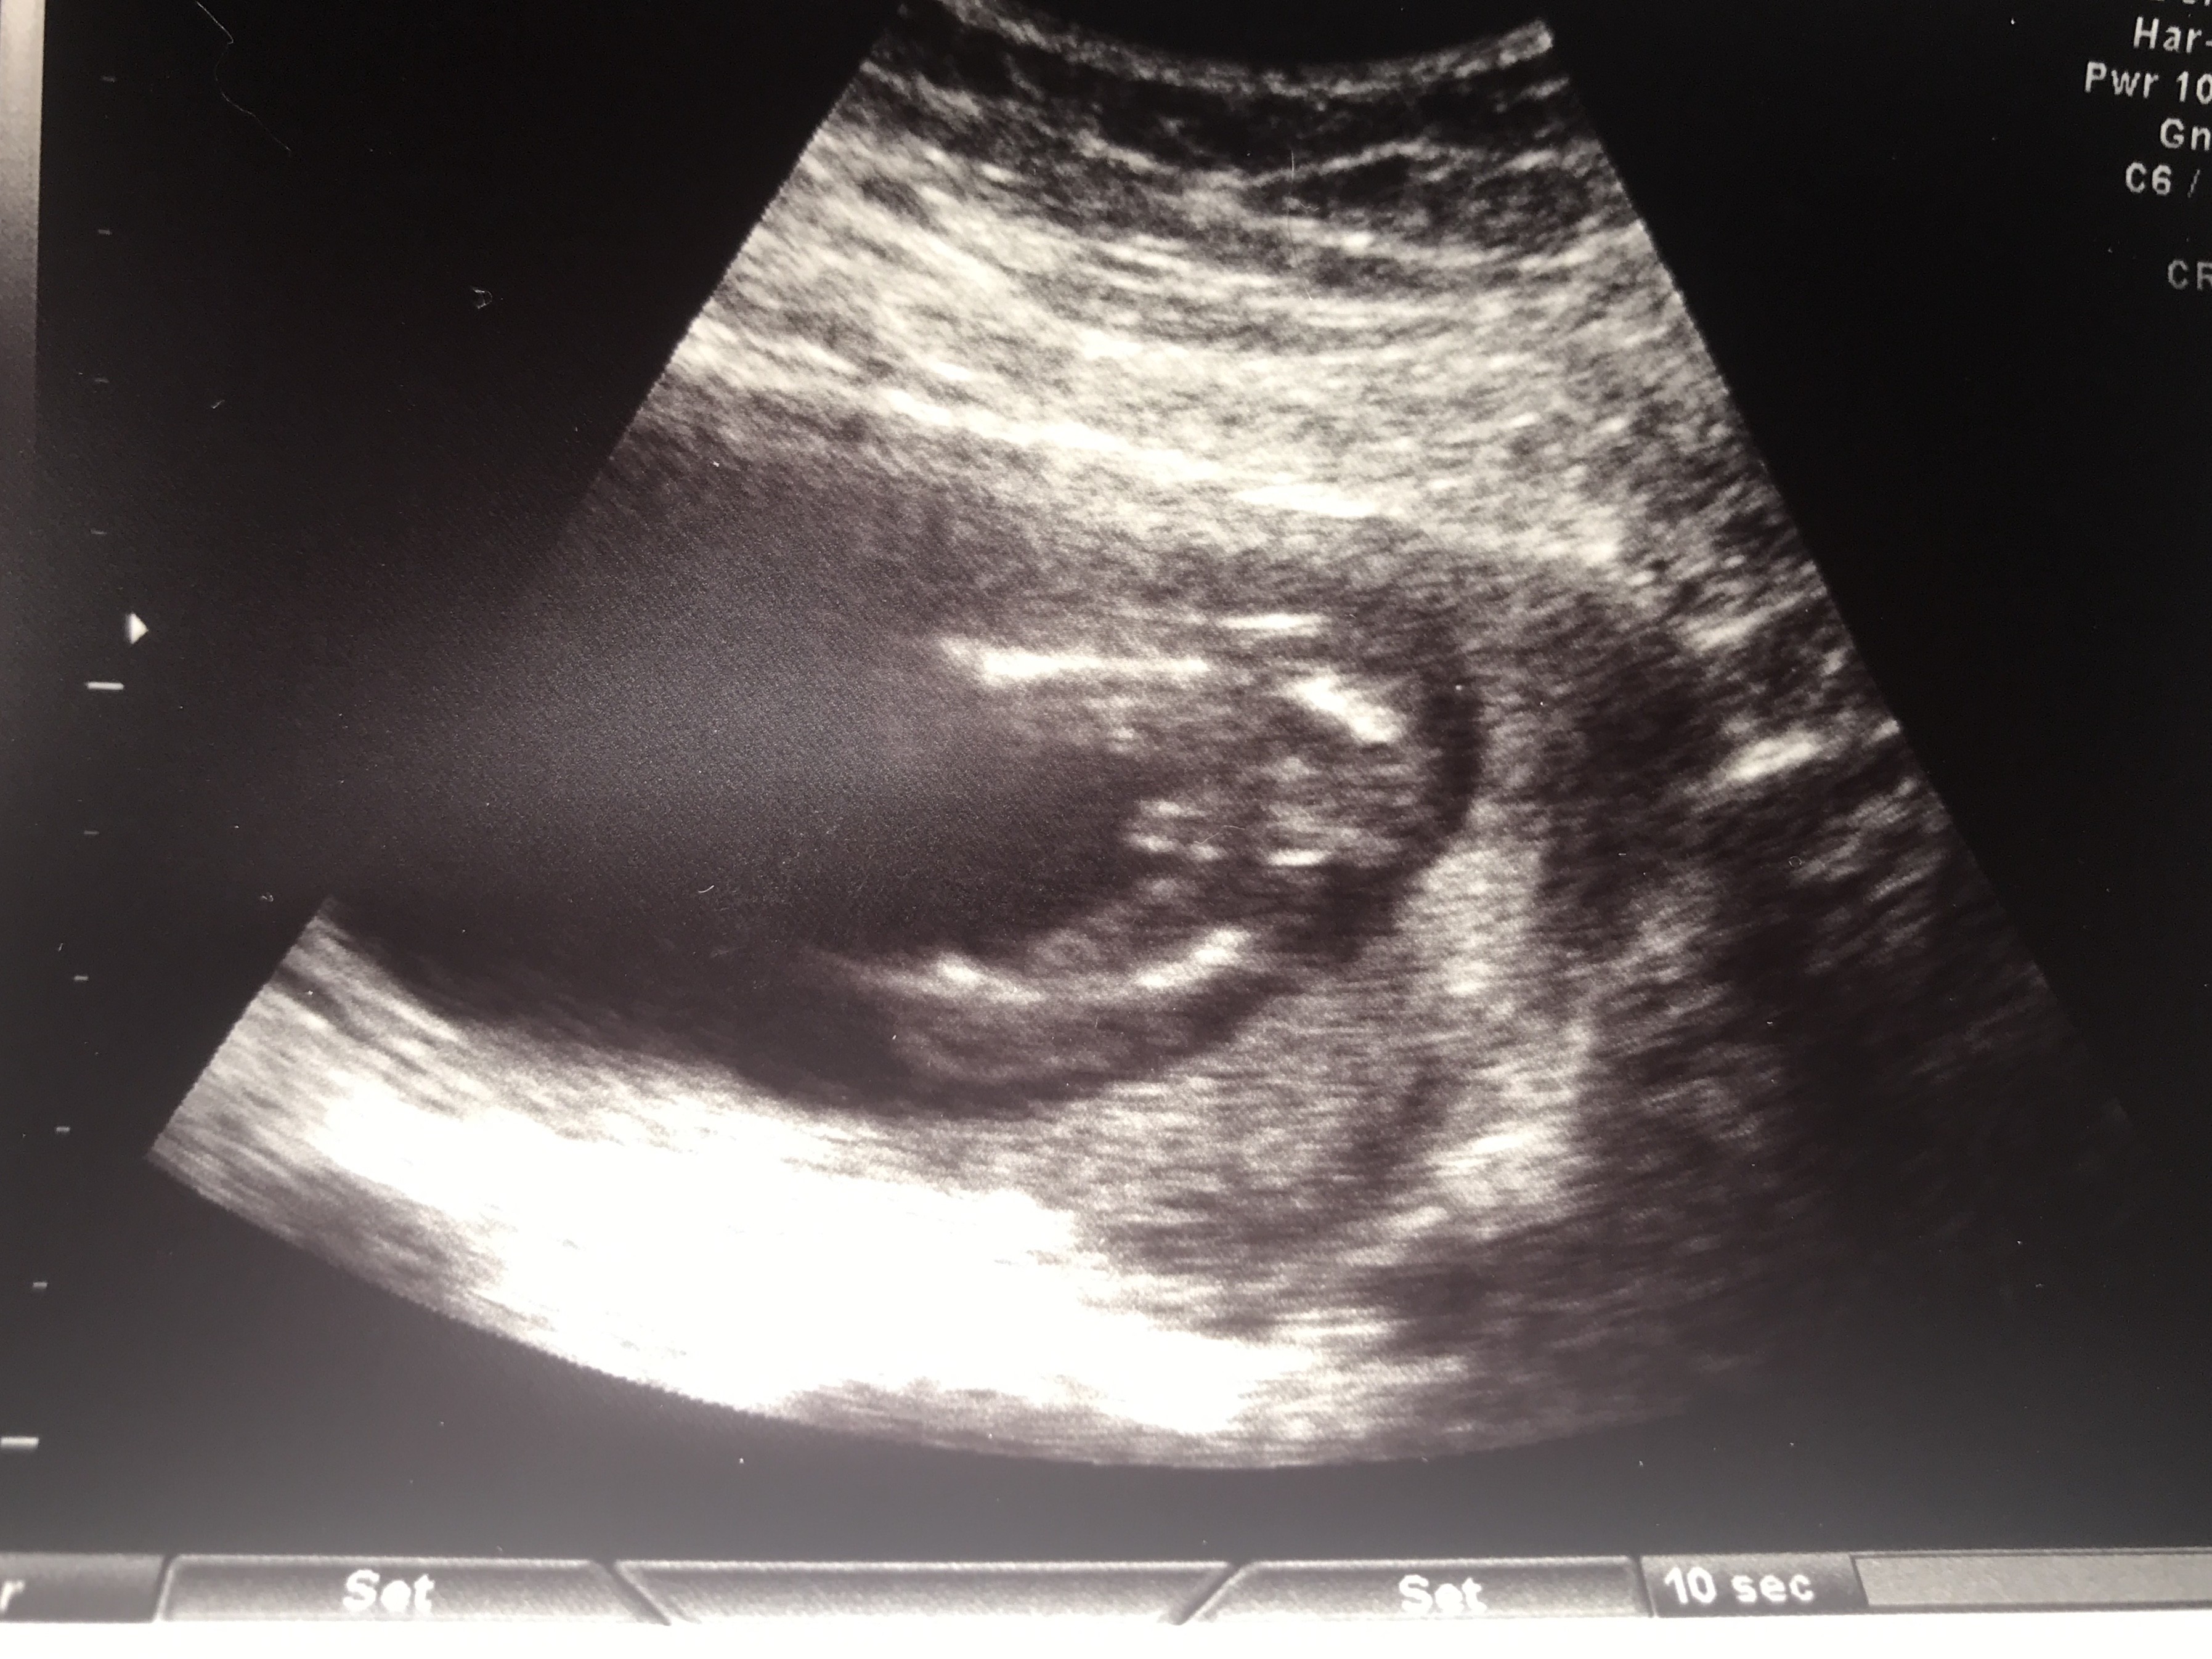

Witam w 19 tygodniu ciąży dowiedziałam się ze będę miała dziewczynkę w 20 tyg okazało się jednak , że to chłopak. Sama już nie wiem bo na jednym usg widać na pewno dziewuche a na drugim chłopca. Może to pempowina ?? Może ktoś mi pomoże rozwiązać ta zagadkę